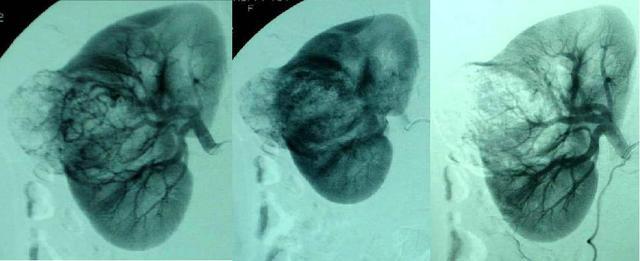

栓塞治療是在醫(yī)學(xué)影像設(shè)備引導(dǎo)下(X線、CT、超聲、MRI),利用穿刺針、導(dǎo)管、導(dǎo)絲、支架以及其他介入治療器材,抵達(dá)病灶后,注入藥物,阻止血流進(jìn)入良性腫瘤或畸形部位供養(yǎng),達(dá)到“餓死”病變部位的效果。在世界范圍內(nèi)被廣泛應(yīng)用,美國(guó)國(guó)務(wù)卿賴斯得了子宮肌瘤就是用介入栓塞治療好的。

目前栓塞治療是介入放射領(lǐng)域三大技術(shù)之一(另外兩大技術(shù)是經(jīng)動(dòng)脈灌注術(shù)和經(jīng)導(dǎo)管減壓術(shù)),栓塞治療是現(xiàn)代介入診治中重要的醫(yī)學(xué)技術(shù)。